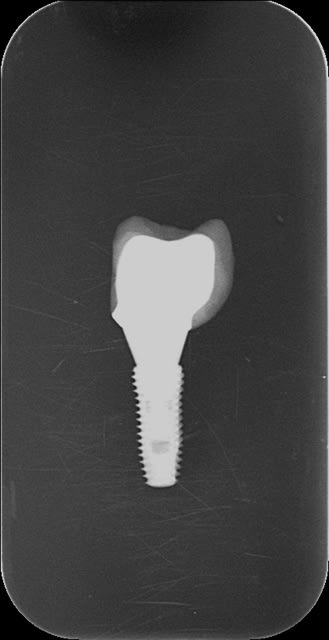

ci joint 2 clichés ( médiocre)

une connectique astra et un transfert dentium .

tout deux identique en tout point à l'exception de la partie

hexagonal

Sur l'astra , elle fait 1.5 mm et va jusqu'au bout

alors que sur le dentium elle mesure 0.7 et le bout se termine

par un cylindre biseauté..

Et bien dans le premier cas l'emboîtement se fait de manière instantané alors que sur le dentium il faut "trouver" en tournant la les deux partie jusqu'à ce qu'elle s'emboîte ..

Ce n'est pas grand chose quand on a un analogue et un pilier dans la main mais sur un modèle ou en bouche avec les tissus c'est une autre histoire...

Est ce pour une histoire de copyright ou bien volontairement dans un but technique .....

pluton avais tu remarqué ce détail?